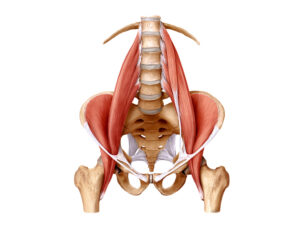

Un solo muscolo, tante funzioni

Lo psoas è un muscolo involontario, grande e potente,

Lo psoas è un muscolo involontario, grande e potente,

al centro del corpo. Si origina lateralmente

alla colonna a livello dell’ultima vertebra toracica e

include tutte le vertebre lombari.

Passa dietro ai visceri, sotto il legamento inguinale e

si inserisce facendo una curva a spirale nel femore.

A lui dobbiamo diversi movimenti dell’anca e del

tronco e, in più, garantisce la stabilità della colonna

agendo da tirante come fosse una tenso-struttura.

Inoltre, crea un piano, il “piano psoatico”, per il supporto

dei visceri: influenza e viene influenzato dal viscere,

tanto da essere chiamato “muscolo spazzino” perché assorbe e può rilasciare a sua volta stress al

colon e ai reni. Costituisce, nel suo funzionamento ottimale, una pompa idraulica che massaggia gli organi durante la

deambulazione, così come è collegato ai pilastri del diaframma.

Liz ritiene che i muscoli psoas siano le “radici” della

linea mediana, la base della nostra integrità, coerenza

e risorsa fondamentale: osservate la posizione anatomica dei muscoli psoas nell’immagine sopra e comprenderete il fondamentale

ruolo di collegamento tra il nostro centro “ombelico-diaframma-plesso solare” e la nostra mobilità,

l’andare verso le gambe guidate dal sistema nervoso. diaframma respiratorio. Infine, è influenzato dagli

Ora visualizza il grande psoas, con l’aiuto dell’illustrazione anatomica .